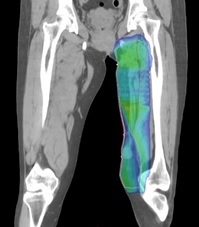

大腿原発の悪性軟部腫瘍術後。再発を防ぐための術後照射。